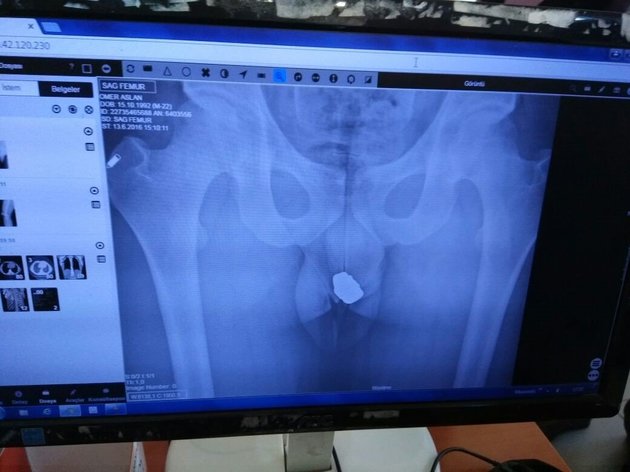

A suspected jewel thief in Konya, Turkey, has been arrested after stolen rings and necklaces were found in his rectum during an X-ray exam, police said.

The 24-year-old was taken to a local hospital to be examined by an X-ray technician, according to the Anadolu Agency.

The technician found several objects in the suspect’s rear end, including two gold rings, four gold earrings and two gold necklaces.

In an amazing coincidence, those objects belonged to the technician’s family, according to Hurriyet.com.tr, a Turkish language website.